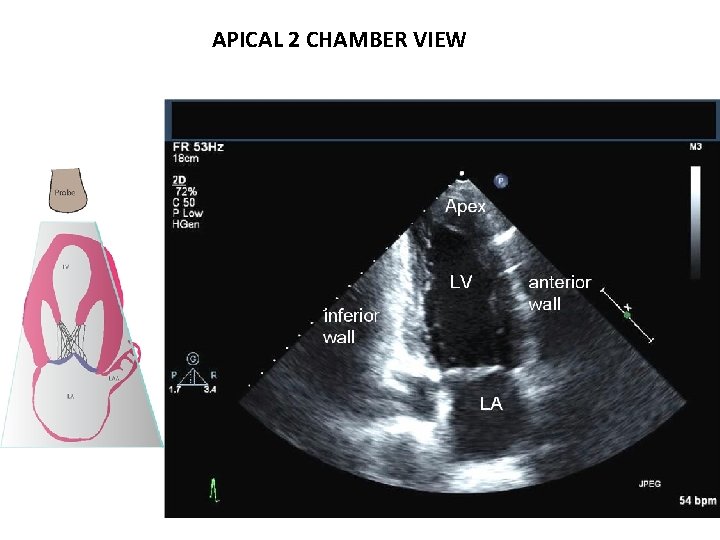

APICAL 2 CHAMBER VIEW

APICAL 2 CHAMBER VIEW – OFF AXIS POSTERIOR TILT, MEDIAL ANGULATION, COUNTERCLOCKWISE ROTATION

APICAL 2 CHAMBER VIEW LA APPENDAGE